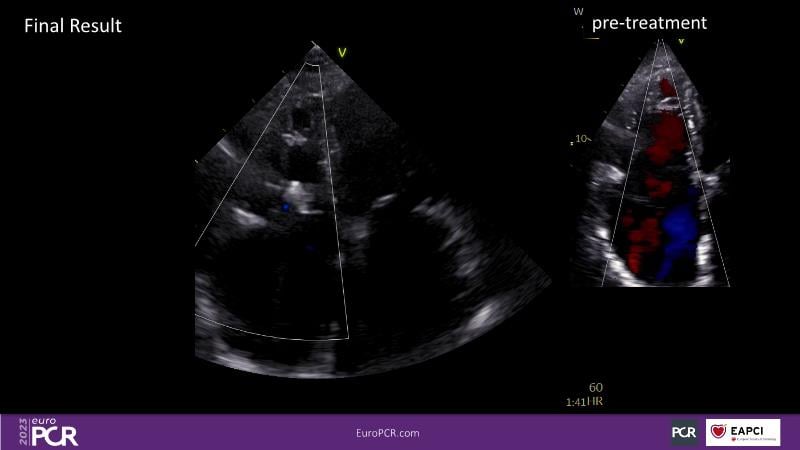

Watch this session to discuss exciting cases of tricuspid regurgitation, learn about the proposed new integrated classification for tricuspid regurgitation and enjoy a live presentation of the PASCAL Precision Repair System using a beating heart simulator, among others!

- To discuss the different tricuspid regurgitation phenotypes that can be treated with the PASCAL Precision repair system

- To participate in a case-based discussion using the PASCAL Precision repair system for the treatment of tricuspid regurgitation